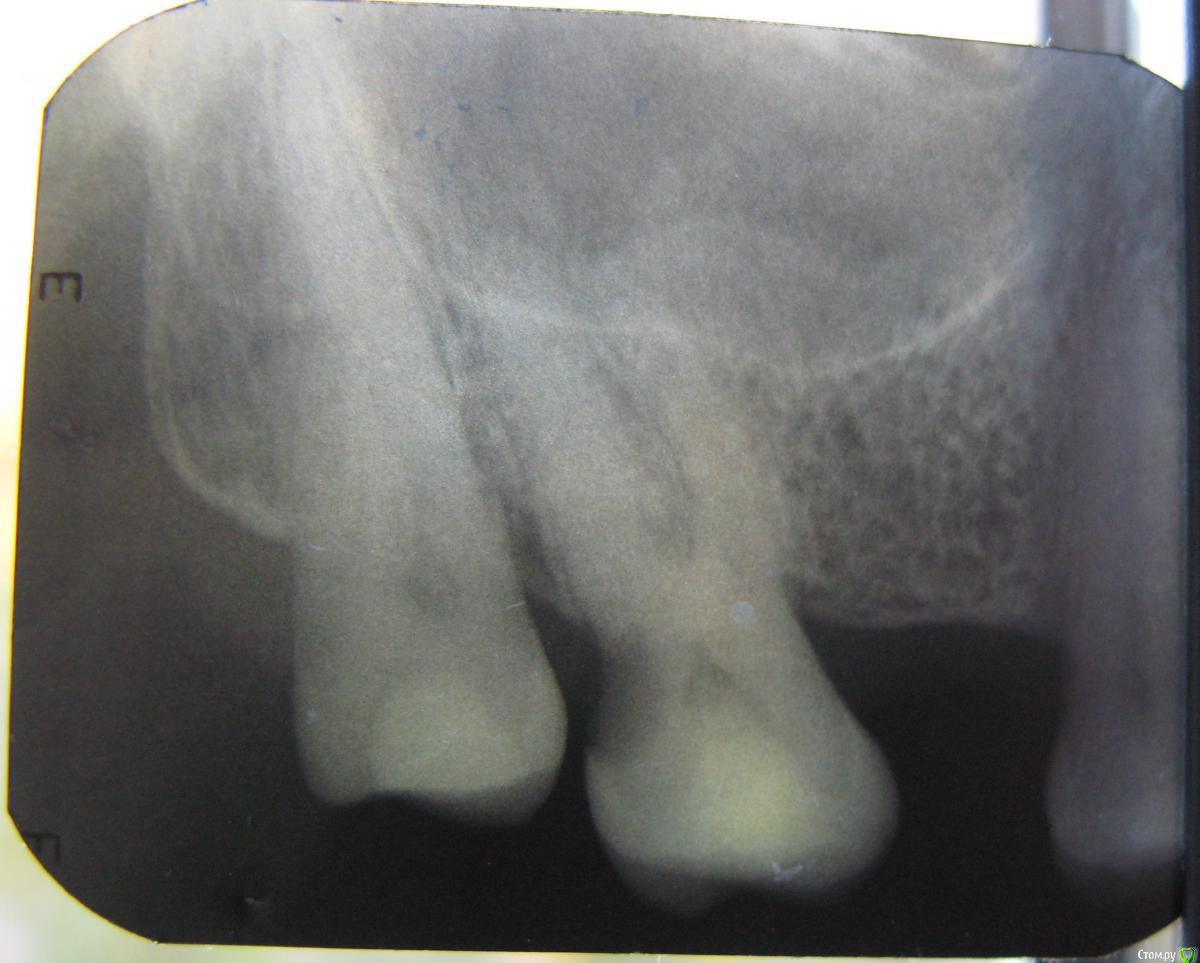

vica17 Опубликовано 11 октября, 2015 Поделиться Опубликовано 11 октября, 2015 (изменено) Добрый день.Прошу специалистов проконсультировать по 27-му зубу.Два месяца назад пошла к доктору для лечения, поставлен был пульпит, зуб рассверлен, установлено, что нервы уже мертвые (был большой многолетний карман со стороны 28 зуба), по запаху доктор определил воспалительный процесс, чистились каналы, заложено лекарство (какое - не знаю). Затем через две недели открыли каналы и установили, что в небном канале есть еще воспаление, при прочистке этого канала было больно и ощущение укола, поставлена временная пломба на 1 месяц. Это было 18 августа. Через 2 недели начался гайморит, потом ставили синусит, пропила сначала 5 дней Цифран СТ, потом через 2 недели назначили Амоксиклав 625мг 7 дней. Анализы отличные, из носа ничего не текло и не течет. Может синусит и не из-за зуба, хотя раньше никогда таких проблем не было, ЛОР определенно не утверждает ничего. Сейчас осталась небольшая ломота в носу с левой стороны (там где зуб). С зубом теперь не знаю, что делать. Была на консультации в двух клиниках (не там, где лечила). Везде сказали, что кариес не убран "зачем лечили каналы, не убрав кариес?". Рекомендации - одна - удалять, другая - можно попробовать полечить с микроскопом, но без гарантии. Зуб до манипуляций не болел совсем, теперь ощутимо и немного болезнено боковое нажатие, хотя накусывание не больно, жевать им могу нормально. Немного ломит скула, но это может остатки от ринита-синусита.Пожалуйста, посоветуйте, есть ли смысл спасать зуб, или шансов нет?Снимок до начала лечения Снимок после двух чисток каналов, пломба временная Заранее благодарна за консультацию. Изменено 11 октября, 2015 пользователем vica17 Ссылка на комментарий

sydnik Опубликовано 11 октября, 2015 Поделиться Опубликовано 11 октября, 2015 здравствуйте!на обоих снимках каналы не лечены!может перепутали чего! 2 Ссылка на комментарий

vica17 Опубликовано 11 октября, 2015 Автор Поделиться Опубликовано 11 октября, 2015 здравствуйте!на обоих снимках каналы не лечены!может перепутали чего!Нет не перепутала, чистили 2 раза, положили лекарство, но не пломбироали еще. Из-за синусита остановилась в лечении. Ссылка на комментарий

vica17 Опубликовано 11 октября, 2015 Автор Поделиться Опубликовано 11 октября, 2015 Наверное я неправильно указала, каналы два раза чистили, но не пломбировали окончательно. Сейчас временная пломба и кариес остлся, как и был с самого начала. Не знаю что теперь с этим делать. Ссылка на комментарий